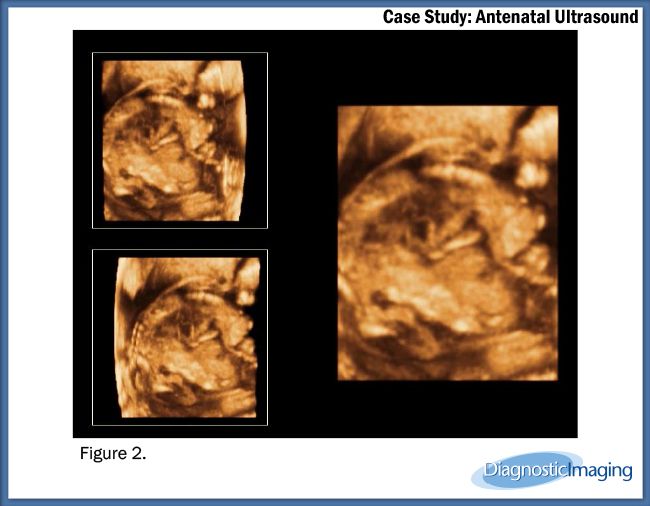

Case History: 25-year-old patient presents for antenatal ultrasound.